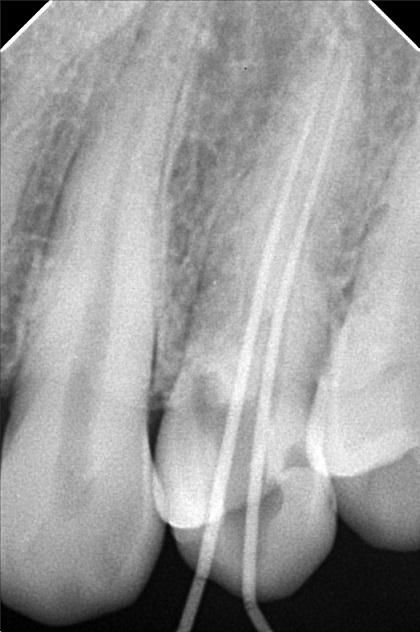

Edit Record Check our patient data records. Add patient information Patient Info Profile picture Last Name First Name Middle Name Birthdate Age Street Barangay City Country Zip Code Contact number Email Procedure 02/08/22- Resto Lc 14 MO+ CAOH/ 24 MO/ 28 O 7/8/22- Broach, 2 Canals, Pulp devitelizer, eugenol 7/15/22- 23 buccal, 23 lingual stop at 25 file , campenol - 7/22/22 - CAOH dressing. 30mm file 08/10/22- obturation/ 23mm resto 24 occlusal/ Lc 22 lingual File anthonygarcia.docx File 2 299444183_756856052263890_2466150992968737449_n.jpg File 3 anthony_garcia.jpg File 4 anthony_garcia_1.jpg File 5 File 6 File 7 File 8 File 9 File 10 File 11 File 12 File 13 File 14 File 15 File 16 File 17 File 18 File 19 File 20 Retain Record Retain Record Yes No Save Your Changes